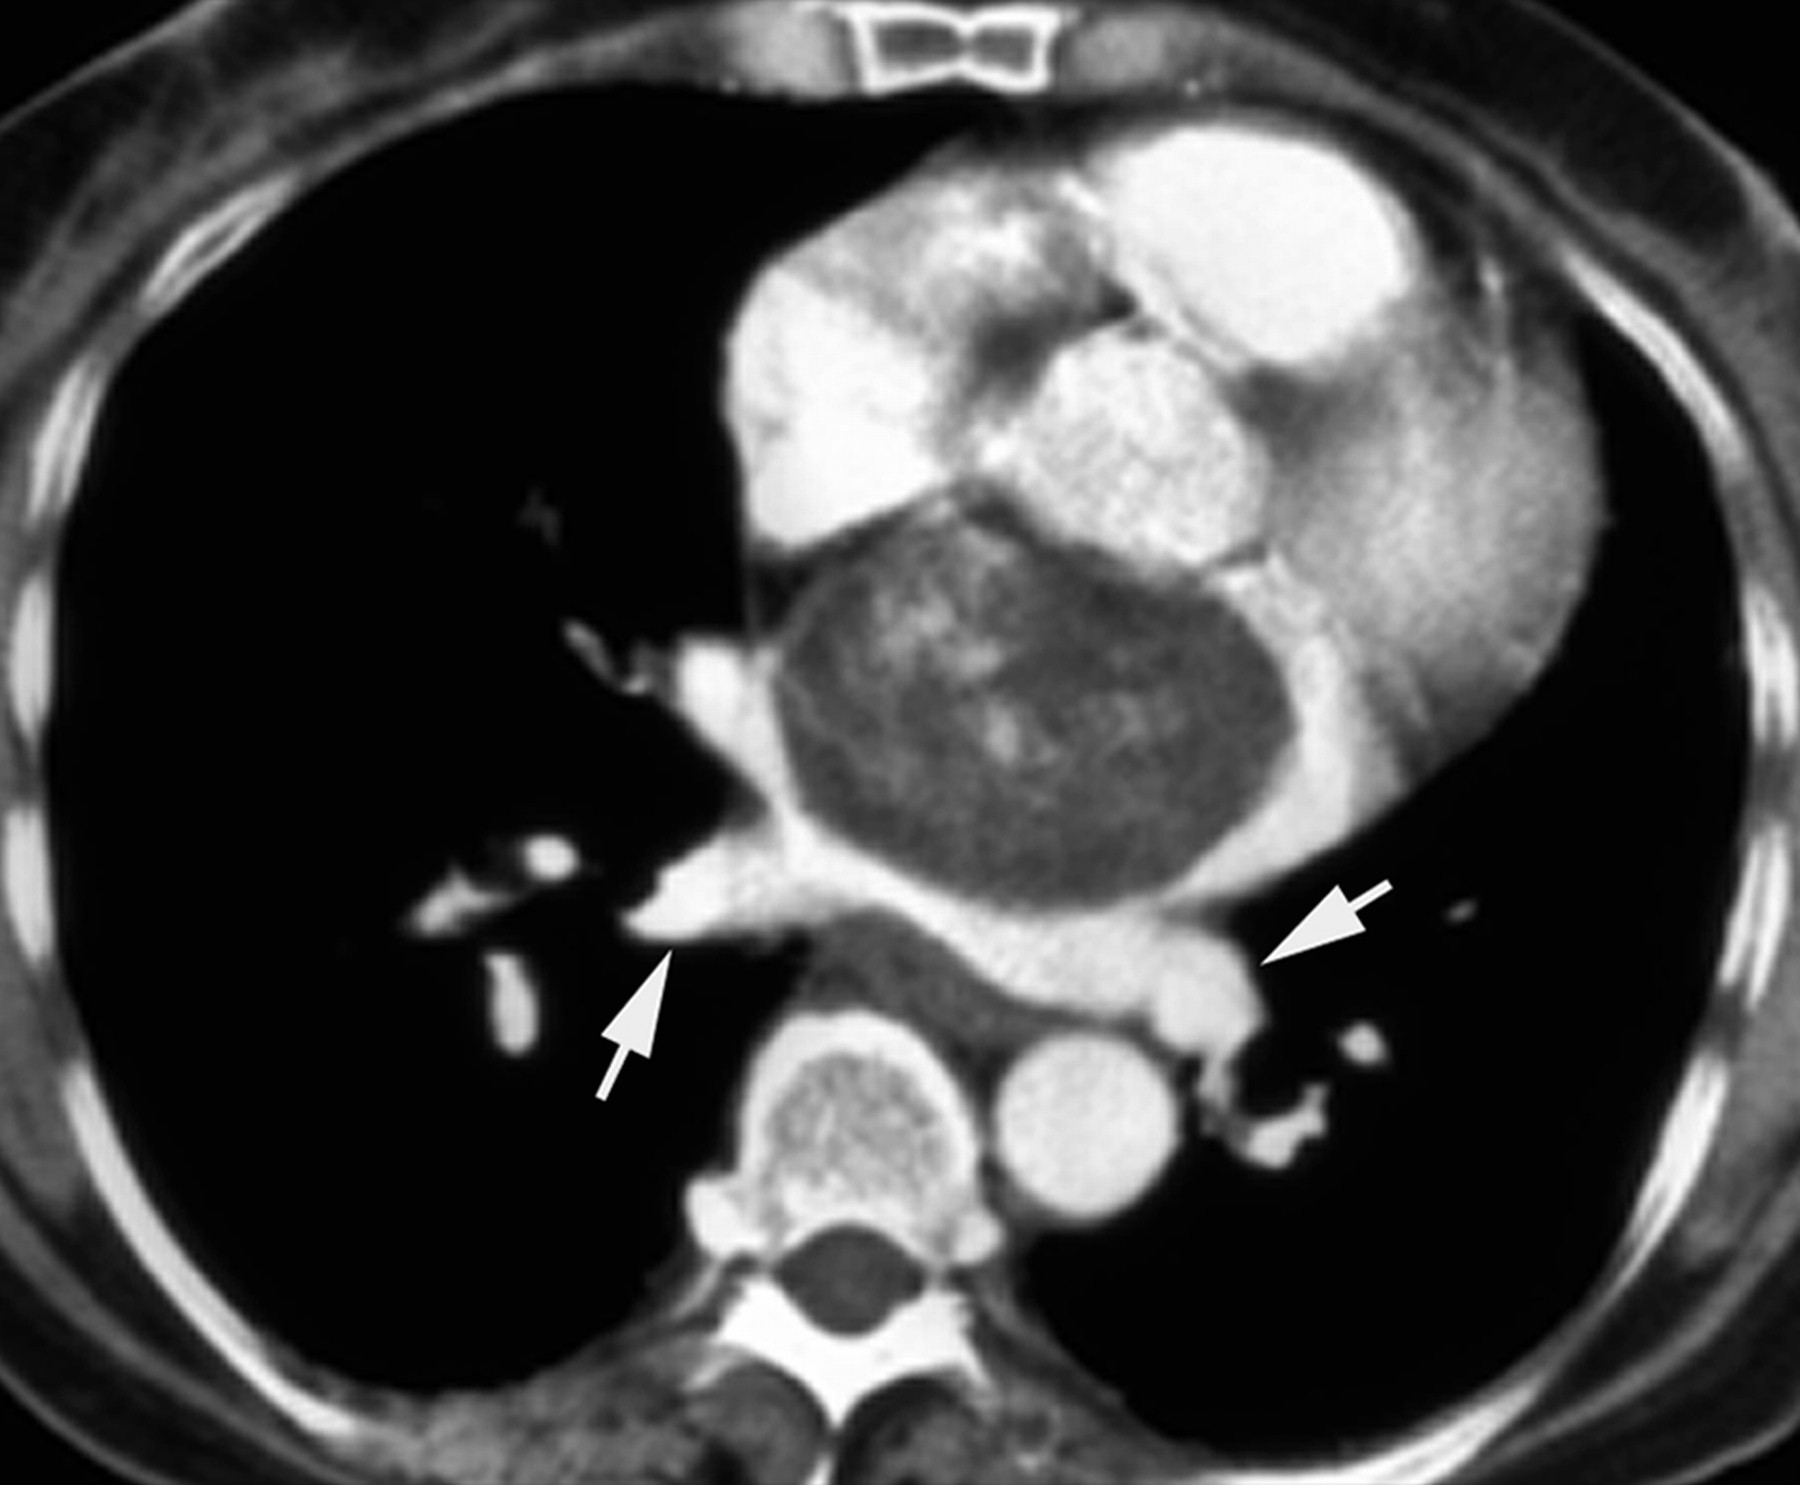

ID: 11275 Cardiac myxoma Radswiki - 20 Oct 2010 CT demonstrate a cardiac myxoma in the left atrium This c...